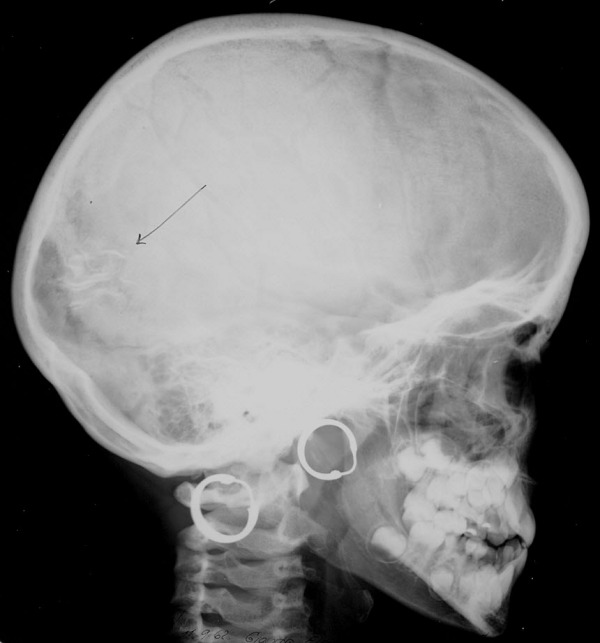

Sturge Webersche Krankheit Sturge Weber Syndrom Springermedizin De

Sturge Webersche Krankheit Sturge Weber Syndrom Springermedizin De from media.springernature.com